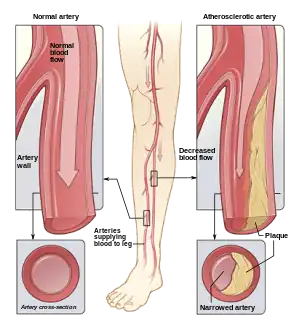

Arterial Diseases

Sonodynamic therapy could be used to treat more than just cancers. Atherosclerosis, which is a chronic arterial disease, is another target that has been observed in the literature.[3][5] This disease occurs when fatty plaques aggregate on the inner surface of the artery and could be caused by malfunctions in lipid metabolism.[3] More specifically, atherosclerosis is caused by an increase in endothelial permeability causing low-density lipoprotein particles to become oxidized and undergo sedimentation.[3] These lipoproteins cause an increase in macrophages and lead to intensified plaque build up. As a result, the high influx of macrophages is the target for AS treatment in order to slow plaque build-up.[3] Alongside the relationship between plaque build-up and macrophages, monocyte's differentiation into macrophages exacerbates the aforementioned process in addition to causing inflammation.[3]

A study by Wang et al. aimed to understand the underlying mechanisms regarding the potential effect of non-lethal SDT on atheroscleroic plaques. It was determined that non-lethal SDT prevents plaque development.[5] A study performed by Jiang et al., showed success in SDT through the reduction of macrophage inflammatory factors such as TNF-alpha, IL-12, and IL-1B. They also showed that SDT could inhibit plaque inflammation in patients with peripheral artery disease and continue to promote positive results for longer than six months.[4] Popular sonosensitizers for AS treatment are protoporphyrin IX (PpIX) and 5-aminolevulinic acid (5-ALA).[69][3] PpIX is often used in PDT and is generated through 5-ALA, a non ultrasound-activated component, through increasing PpIX concentration within a cell. A study by Cheng et al. determined that THP-1 macrophage apoptosis is induced by an increase in PpiX concentration, leading to the production of large amounts of ROS.[70][13][3] The use of SDT for AS treatment has also shown success in promoting the repopulation of vascular smooth muscle cells (VMSCs) through inducing further expression and autophagy to prevent VMSC evolution into plaque-holding macrophages. A study performed by Dan et al. showed the increase in smooth muscle a-actin, smooth muscle 22a, p38 mitogen-activated protein kinase phosphorylation.[71][3] While a study by Geng et al. showed improved VMSC autophagy. Each of these factors contributed to the improved differentiation and development of VMSCs.[3]